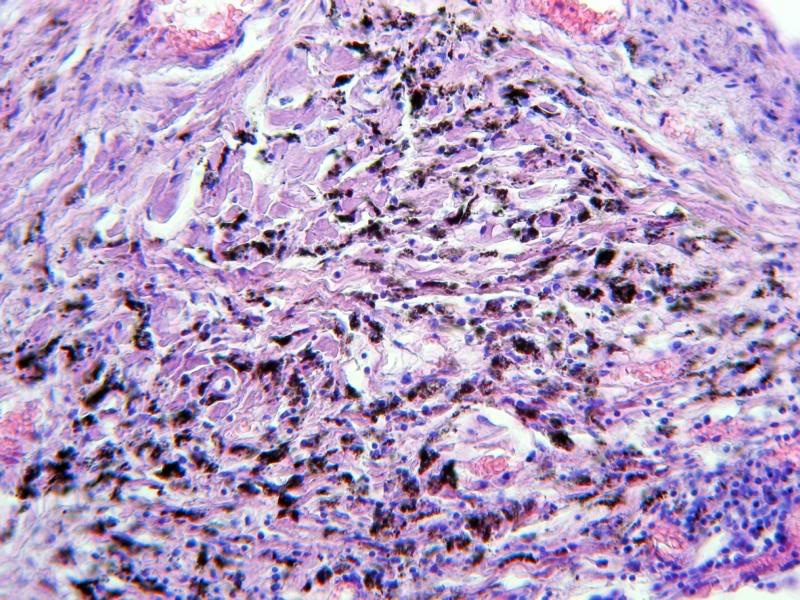

Ihr seht einen Lungenschnitt, der die Anthrakose (auch Staublunge) deutlich zeigt. Dabei handelt es sich um eine Staubinhalationskrankheit. Die vielen schwarzen Punkte sind mit kohlestäuben beladene Makrophagen. Ursache dieser Veränderung ist das häufige Einatmen von Stäuben z.B. aus Autoabgasen oder auch Zigarettenrauch. Diese Krankheit wurde erstmals bei den Arbeitern der Steinkohleminen festgestellt und erforscht.

Ich hoffe die Bilder gefallen euch. Sie sind zwar nicht ganz optimal, aber das wesentliche erkennt man. Zum Histologischen kann ich euch leider nicht mehr erzählen, dazu fehlt mir einfach das Wissen. Ich finde es aber trotzdem sehr interessant, sich diese Ablagerungen anzusehen. Die Bilder selbst wurden alle mit meiner A540 am Zeiss Standard gemacht und mit PSE 5.0 leicht nachbearbeitet.